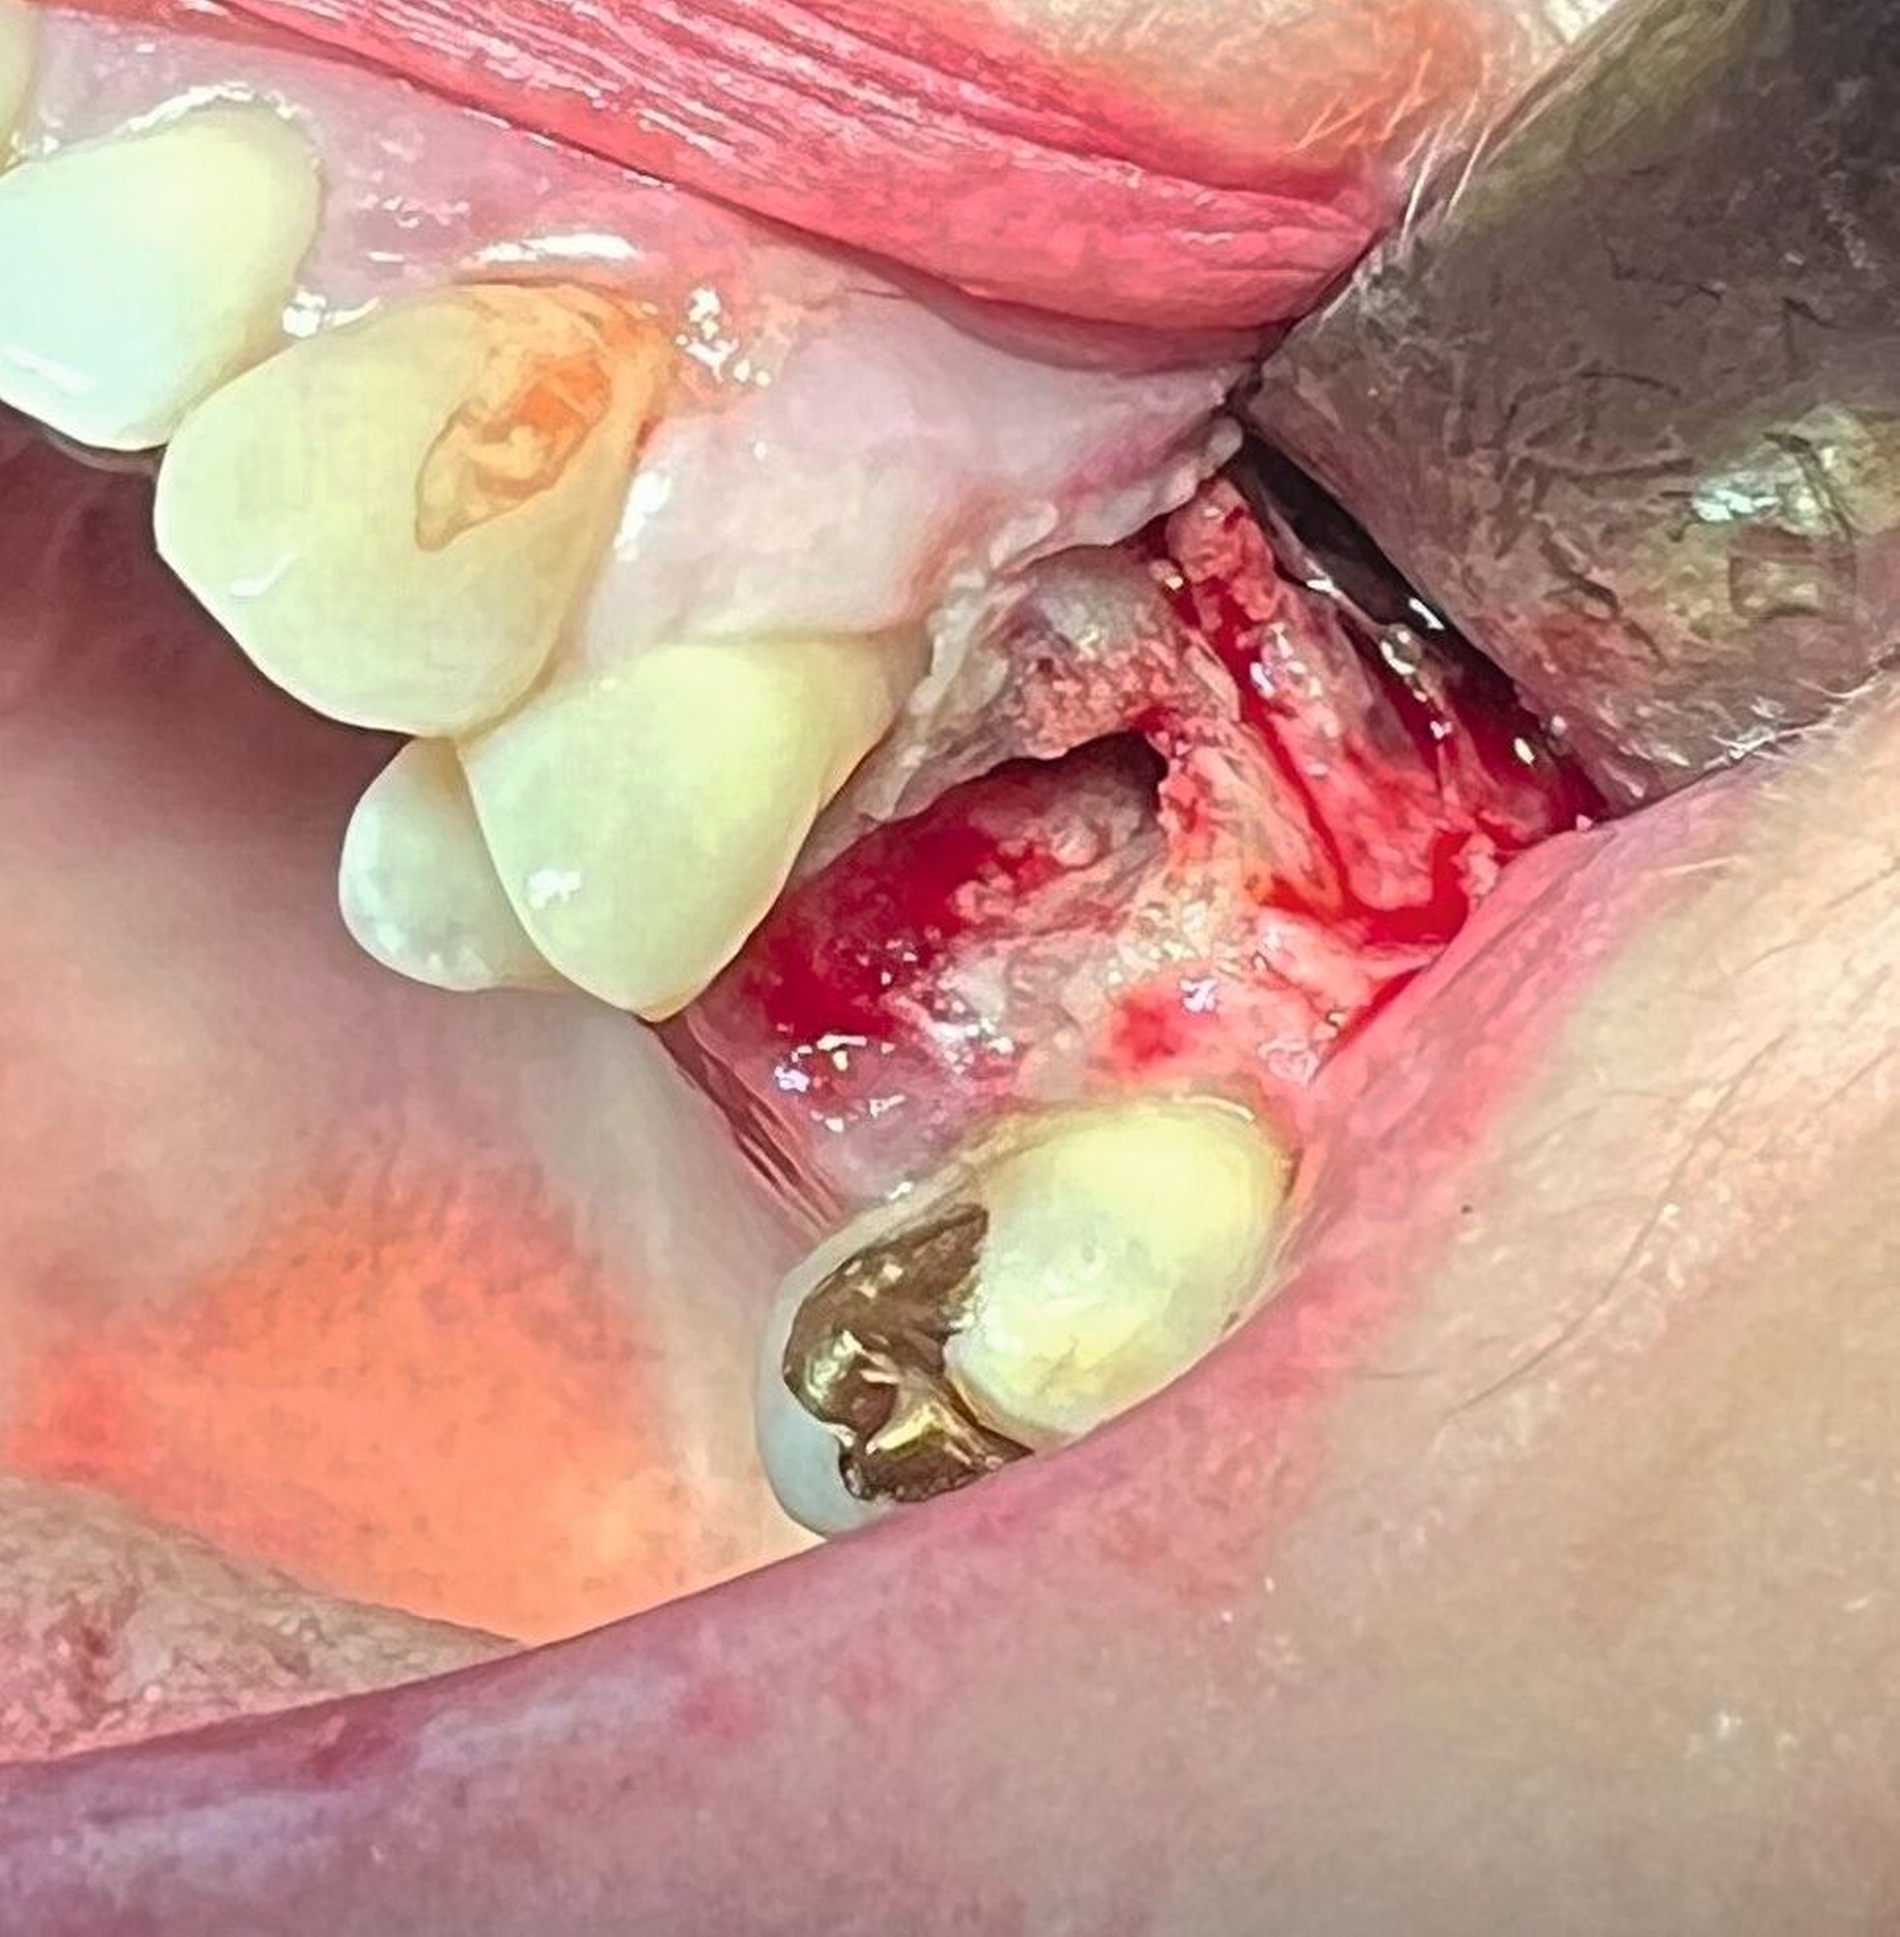

Das präoperative OPG zeigte einen generalisierten horizontalen und an den Zähnen 16 und 26 auch einen vertikalen Knochenabbau, Konkremente insbesondere im zweiten und im dritten Quadranten und in der Unterkieferfront, einen Füllungsverlust an 22, eine regelrechte Wurzelkanalbehandlung an Zahn 25, aber keine weiteren Auffälligkeiten in den umgebenden radiologischen Strukturen (Abbildung 2). Unter antibiotischer Abschirmung wurde der nekrotische Knochen einschließlich des Zahnes 25 bis zum vitalen, durchbluteten Gewebe in Lokalanästhesie abgetragen (Abbildung 3). Der Wundverschluss erfolgte mittels eines Dehnungslappens durch Periostschlitzung (Abbildung 4). Es folgte eine detaillierte Instruktion zur postoperativen Wundschonung. Eine Röntgenkontrolle wurde postoperativ durchgeführt (Abbildung 5).